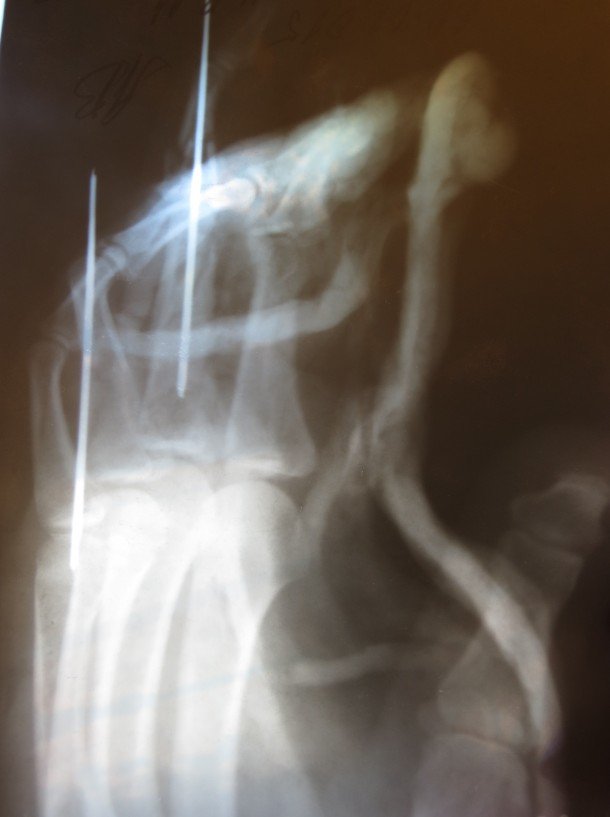

Поки прийшов до тями від побаченого – нагодились побратими, які й дістали Валерія. За деякий час його вже передали медикам і повезли до лікарні в Артемівськ. Фактично за годину часу він двічі стояв на порозі смерті – спочатку снайперська куля, а потім «Град». Після вибуху в голові позастрягали уламки бетону, окремі з яких по сьогодні не видалили. Однак найтяжчим все ж таки виявилось кульове поранення руки. Пострілом роздробило суглоби, тож пальці просто висіли. Лікарі в Артемівську зробили операцію. Вже згодом хлопця перевезли до Харкова. В руку вставили шпиці Кіршнера, однак пальці всеодно лишились деформованими.

Зокрема, у Валерія відсутня нігтьова фаланга на другому пальці, а роздроблені суглоби зрослись з кістками.